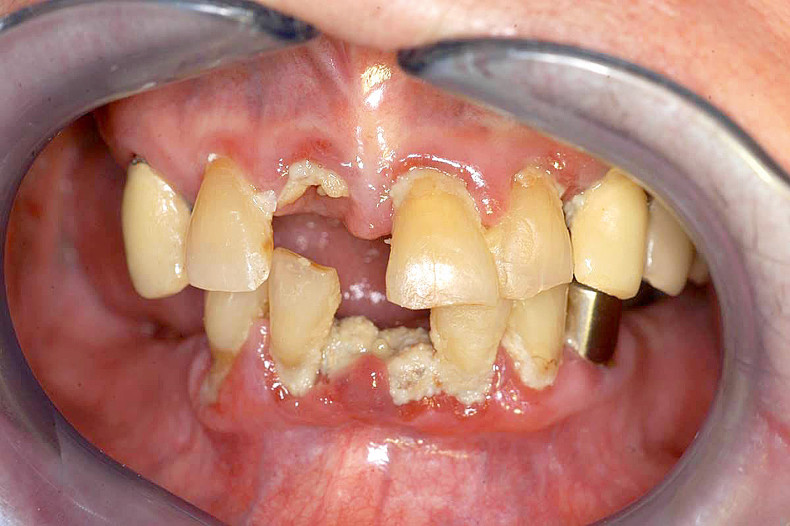

Karies bei Störungen der Speichelsekretion

Zu den charakteristischen Problemen bei Allgemeinerkrankungen (wie Diabetes) oder bestimmten Medikationen (z. B. blutdrucksenkende oder antidepressive Medikamente und bestimmte Psychopharmaka) gehören kariöse Läsionen an Glattflächen sowie die Wurzelkaries. Häufig treten diese in Verbindung mit einer verminderten Speichelsekretion (Xerostomie) auf. Als Folge der fehlenden protektiven Wirkung des Speichels entwickeln sich kariöse Läsionen bei Xerostomiepatienten 15-mal so schnell wie bei gesunden Kontrollpersonen.12 Die rasche Progredienz ist durch die fehlende Pufferkapazität des Speichels zu erklären. Bei nachlassender Remineralisationsfähigkeit und gleichzeitig steigenden Plaqueansammlungen können Demineralisationen vermehrt an sonst wenig kariesanfälligen Flächen entstehen (Abb. 1a–c).13

Gingivale Wucherungen

Als Folge einer antihypertonen Therapie mit Kalziumkanalblockern (Nifedipin), immunsuppressiven Medikamenten (Ciclosporin A) oder bei einer Medikation mit bestimmten Psychopharmaka (trizyklische Antidepressiva, Hypnotika und Sedativa) können bei den dafür empfänglichen Patienten gingivale Veränderungen (Wucherungen) auftreten. In fortgeschrittenen Fällen können diese die Durchführung der Mundhygiene und Therapie von kariösen Defekten in unmittelbarer Nähe der Gingiva erschweren (Abb. 1a und 3a).9

Therapie gingivaler Wucherungen

Die im Verlauf einer antihypertonen oder antikonvulsiven Arzneimitteltherapie auftretenden gingivalen Wucherungen werden zunächst konservativ durch eine supra- und subgingivale Belagentfernung behandelt (Abb. 1a–c, 3a und b). Erst wenn nach wiederholten professionellen Zahnreinigungen mit Mundhygieneanweisungen weit ausgedehnte, medikamentös induzierte, gingivale Wucherungen die Kaufunktion beeinträchtigen und eine Zahnpflege erheblich erschweren, ist eine chirurgische Reduktion durch eine Gingivektomie und Gingivoplastik unumgänglich.